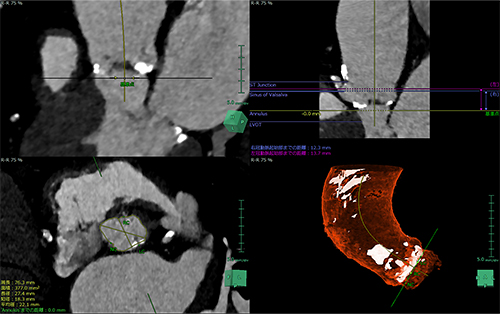

大動脈弁の各種計測や解析をし、大動脈弁置換術を支援します。